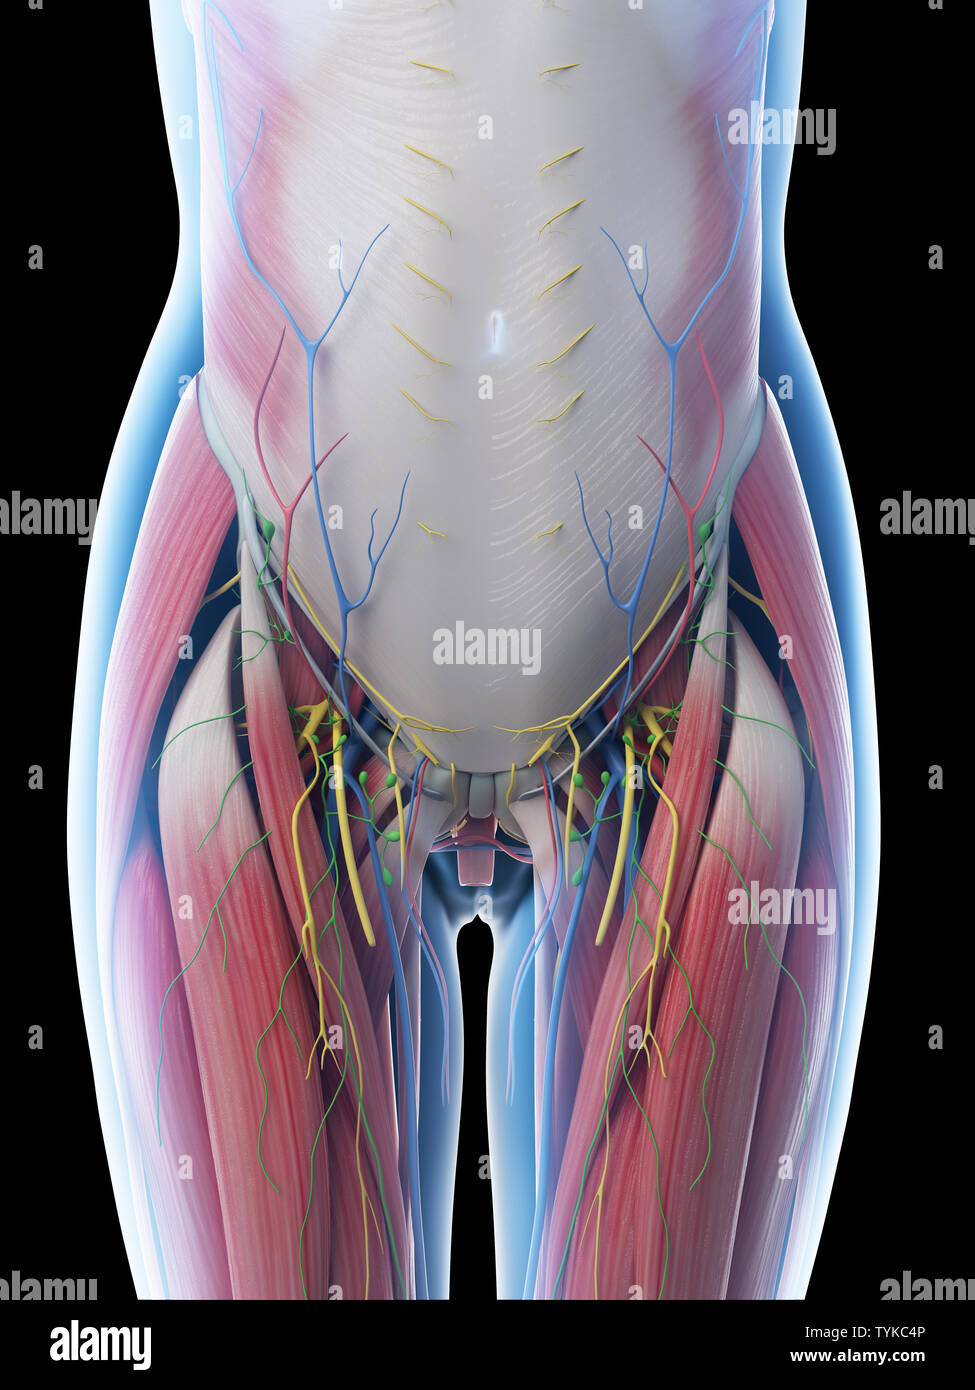

Rendu 3d illustration d'une anatomie de l'abdomen des femelles Banque D'Imageshttps://www.alamyimages.fr/image-license-details/?v=1https://www.alamyimages.fr/rendu-3d-illustration-d-une-anatomie-de-l-abdomen-des-femelles-image257967494.html

Rendu 3d illustration d'une anatomie de l'abdomen des femelles Banque D'Imageshttps://www.alamyimages.fr/image-license-details/?v=1https://www.alamyimages.fr/rendu-3d-illustration-d-une-anatomie-de-l-abdomen-des-femelles-image257967494.htmlRFTYKC4P–Rendu 3d illustration d'une anatomie de l'abdomen des femelles